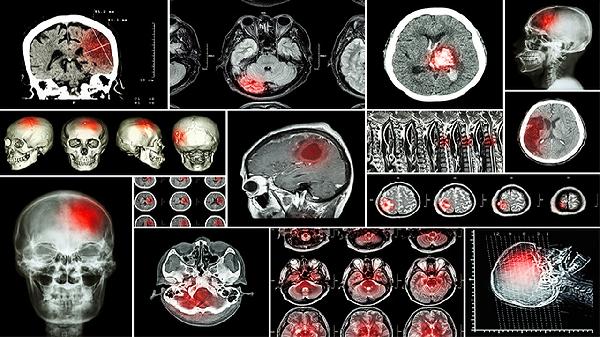

脑肿瘤手术成功率多少,能治好吗

脑肿瘤手术的成功率通常取决于肿瘤类型和手术难度。良性肿瘤如脑膜瘤、垂体瘤等边界清晰,完整切除后复发概率低,术后5年生存率较高。恶性肿瘤如胶质瘤因浸润性生长,手术难以彻底清除,需配合放疗、靶向治疗等综合干预。手术风险与肿瘤位置相关,功能区肿瘤可能影响语言、运动功能,需术中神经监测技术辅助。术后恢复情况与患者年龄、基础疾病有关,年轻患者神经功能代偿能力更强。

脑肿瘤治愈标准需区分良恶性。良性肿瘤全切后多数可临床治愈,定期复查磁共振即可。低级别胶质瘤经规范治疗,部分患者可获得长期生存。高级别胶质瘤即使采用手术联合放化疗,中位生存期仍有限,但新兴电场治疗、免疫疗法可延长生存时间。转移性脑肿瘤需处理原发病灶,预后与原发癌控制情况直接相关。儿童髓母细胞瘤对放化疗敏感,部分病例可实现长期无进展生存。